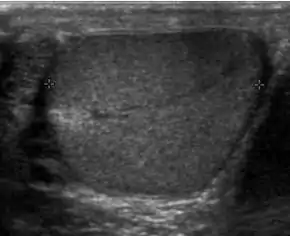

Patients with testicular lymphoma are usually old aged around 60 years of age, present with painless testicular enlargement and less commonly with other systemic symptoms such as weight loss, anorexia, fever and weakness. Bilateral testicle involvements are common and occur in 8.5% to 18% of cases. At sonography, most lymphomas are homogeneous and diffusely replace the testis [Fig. 7]. However focal hypoechoic lesions can occur, hemorrhage and necrosis are rare. At times, the sonographic appearance of lymphoma is indistinguishable from that of the germ cell tumors [Fig. 8], then the patient's age at presentation, symptoms, and medical history, as well as multiplicity and bilaterality of the lesions, are all important factors in making the appropriate diagnosis.

Primary leukemia of the testis is rare. However, due to the presence of blood-testis barrier, chemotherapeutic agents are unable to reach the testis, hence in boys with acute lymphoblastic leukemia, testicular involvement is reported in 5% to 10% of patients, with the majority found during clinical remission. The sonographic appearance of leukemia of the testis can be quite varied, as the tumors may be unilateral or bilateral, diffuse or focal, hypoechoic or hyperechoic. These findings are usually indistinguishable from that of the lymphoma [Fig. 9].

- Fig. 9. Leukemia. Diffuse hypoechoic infiltrative lesions are seen involving the whole testis, indistinguishable from that of the lymphoma.